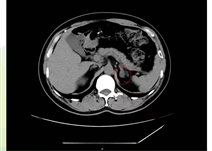

对于肾上腺腺瘤的诊断,需要综合运用多种检查手段。实验室检查如激素水平测定,有助于判断肿瘤是否具有功能性以及分泌的激素类型。影像学检查,如CT、MRI等,能够清晰地显示肿瘤的位置、大小、形态等特征,为诊断和治疗提供重要根据。

如果体检发现肾上腺腺瘤,首先要明确它是否“有功能”:通过CT或MRI明确腺瘤的大小、位置、形态,帮助判断性质。

肾上腺腺瘤CT表现

1.肾上腺腺瘤发生于肾上腺皮质,含脂质;

2.直径多小于3cm;

3.CT值<10HU;

4.出血、坏死、囊变少见;5.CT增强:早期快速廓清